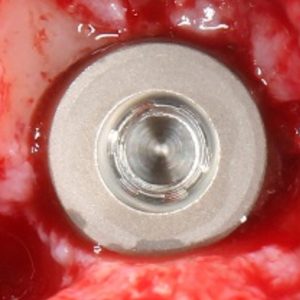

Имплантаты Ankylos имеют совершенно иной тип резьбы. Она имеет квадратно-ступенчатый профиль. Почему?

Изначально Ankylos разрабатывалась как субкрестальная система, для которой первичная стабильность в некоторых условиях (при 3-4 биотипе костной ткани) достигается весьма сложно. Также предполагалось, что имплантат будет находиться ниже слоя кортикальной кости:

и, при этом, он должен удерживаться так, чтобы с ним можно было бы выполнять какие-то манипуляции: снять имплантодержатель, установить заглушку и т. д. Для того, чтобы это было возможно в губчатой кости и, при низкой степени первичной стабильности, не смещаться и не крутиться, нужна высокая площадь контакта, обеспечивающая достаточное трение, при незначительном воздействии на окружающую костную ткань. Это очень похоже на то, как протектор автомобильной шины удерживается на дорожном полотне: